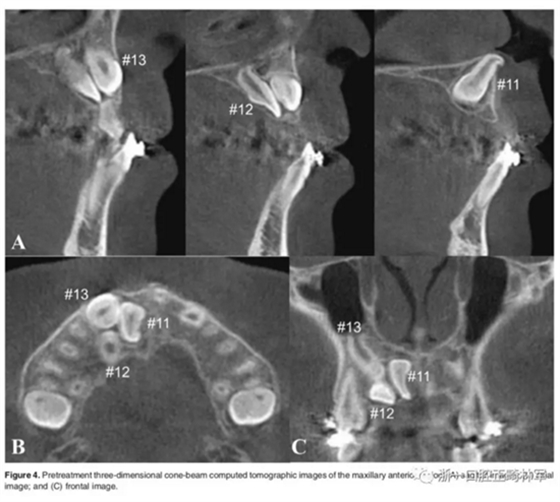

影像檢查:

全景X片及CBCT示:11-13復(fù)雜阻生,上頜前牙區(qū)牙槽骨水平不足;11阻生,遠(yuǎn)中旋轉(zhuǎn)90°,牙冠朝向腭側(cè),根尖位于鼻底、前鼻棘皮質(zhì)骨內(nèi),牙根形態(tài)彎曲;12、13不完全易位,12位置偏腭側(cè),13位置偏舌側(cè),12的牙根形態(tài)也較彎曲。